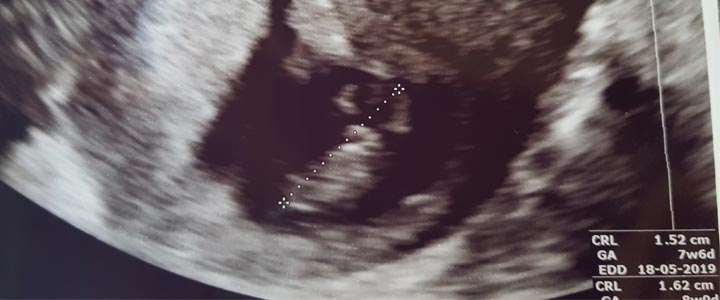

De 6 weken echo – Stel je niet teveel voor van de 6-weken echo

Informatie over de 6 weken echo Heel bijzonder vond ik dat je op internet weinig informatie kunt vinden over de 6 weken echo. Ik begrijp dat niet iedereen recht heeft op deze echo en dat het daarmee ...